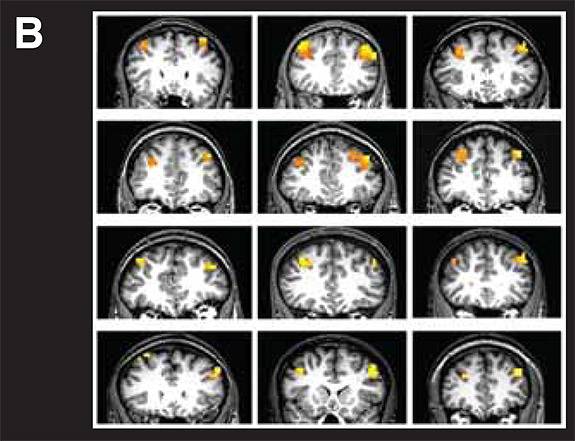

Princeton University researchers have identified mechanisms that govern how the brain incorporates information about new situations into our existing goals. Human volunteers played a game wherein they pressed a specific button depending on a particular visual cue. Functional magnetic resonance imaging showed that updating goals takes place in a region known as the prefrontal cortex. (Photo courtesy of Jonathan Cohen)

To find out, Cohen's team used functional magnetic resonance imaging (fMRI) to scan the brains of human volunteers playing a game wherein they pressed a specific button depending on a particular visual cue. If the volunteer saw the letter A prior to seeing the letter X, he or she had to press button 1. But if the volunteer saw the letter B prior to seeing the X, the participant had to press button 2. The A and B served as the new information that the participant used to update their goal of deciding which button to press. Another version of the task required the same participants to press button 1 upon seeing an X regardless of whether an A or B was shown.

With the fMRI, the researchers detected activity in the right prefrontal cortex during tasks that required the participants to remember whether they saw an A or a B before pressing the correct button, but not during tasks where the participant only had to press the button when prompted by an X.

Finally, the researchers explored their theory that dopamine — a naturally occurring chemical involved in motivation and reward among other brain functions — tags new information entering the prefrontal cortex as important for updating working memory and goals. Cohen and his team imaged a brain region called the midbrain, which contains clusters of nerve cells called dopaminergic nuclei that are the source of most of the dopamine signals in the brain. Using high-resolution fMRI, the researchers probed the activity of these dopamine-releasing cells in the brains of volunteers engaged in the game described above. The researchers found that the brain activity in these areas correlated both with the activity in the right prefrontal cortex and with the ability of the volunteers to press the correct buttons.